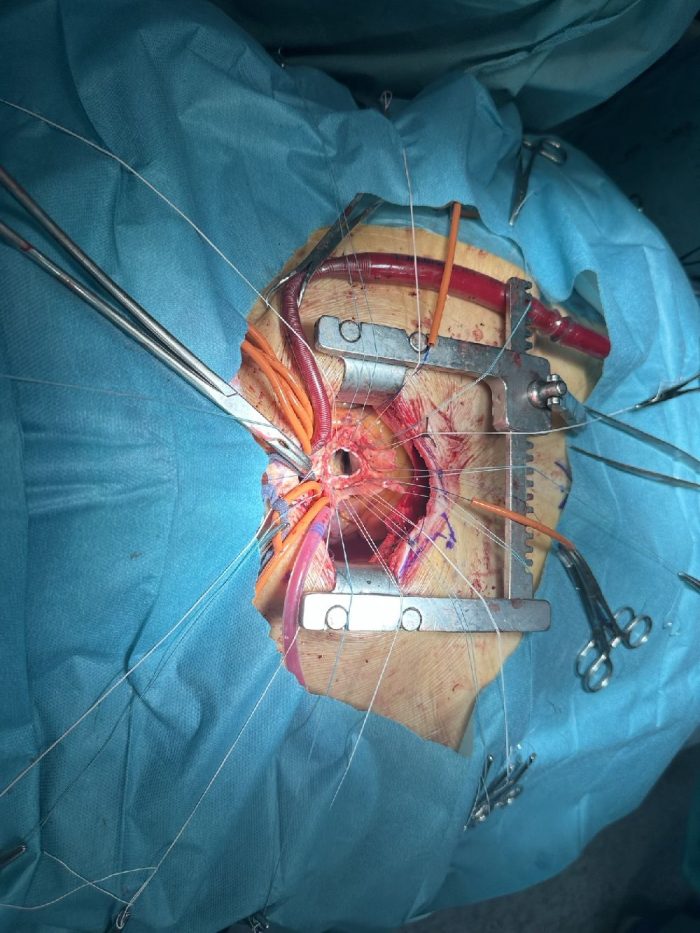

The Mini- Bentall procedure at Clinical Center Tuzla

A team of cardiovascular surgeons at the University Clinical Center Tuzla successfully performed a Mini- Bentall procedure that encompasses aortic valve and aneurysm of ascending aorta replacement, performed via a mini- sternotomy.” Leading surgeon Prof. Dr. Harun Avdagić on this occasion said that this procedure is highly complex and requires skilled surgeons, an experienced surgical…